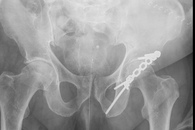

Beckenfrakturen

Beckenfrakturen und Frakturen der Hüftgelenkspfanne (Azetabulum) sind komplizierte, teilweise sogar lebensbedrohende Verletzungen. Schwere, instabile Beckenbrüche treten häufig in Verbindung mit Hochenergieverletzungen wie einem Polytrauma auf. Gefäß- und Nervenverletzungen sind in deren Folge nicht selten und können zu einem massiven Blutverlust führen. Die Erstversorgung hängt von der Schwere der Fraktur und der Begleitverletzungen ab. Bei schweren Verletzungen ist zunächst eine Stabilisierung mit einer Beckenzwinge oder einem Fixateur externe notwendig, um andere Verletzungsfolgen primär zu behandeln.

Zur weiterführenden Diagnostik einer Beckenverletzung steht uns modernste radiologische Bildgebung mit 3D-Rekonstruktion zur Verfügung. Auch intraoperativ ist eine 3D-Bildgebung bei laufender Operation möglich. Zur Therapie von vorderen und hinteren Beckenring-Frakturen favorisieren wir Platten-Osteosynthesen offener Reposition, aber auch minimal-invasive Therapieoptionen und transkutane Verschraubungen.